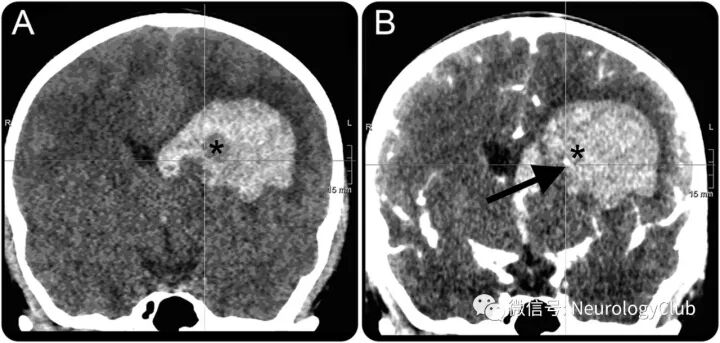

漩涡征

由Al-Nakshabandi于2001年首先描述。定义为CT平扫上2个或以上连续平面高密度血肿内可见低密度区(30-50HU,低或等同于脑实质密度)。近来研究证实,其与脑出血患者血肿扩大相关。

(图6:73岁脑出血患者,最初的头颅CT[A-C]可见左侧顶叶血肿,体积约33ml,其内可见低密度区,即漩涡征;8小时后复查CT[D-F]证实血肿扩大,体积约46ml

10岁女孩,因头痛伴呕吐入院。CT平扫提示脑实质内高密度血肿伴低密度区,符合漩涡征(swirl sign),活动性出血的典型征象(图9)。CT血管造影提示点征(spot sign),符合出血部位活动性造影剂渗漏。随后3小时的CT可见颅内血肿进展(图10)。后患者死亡。尸检证实为凝血因子XIII缺乏症。

漩涡征和点征都是活动性出血的征象,可预测不论年轻还是老年脑实质内出血患者后期血肿扩大,死亡率升高。本例阐释了活动性出血区经典和新征象的一致性。

(图9:CT平扫[A]可见血肿内低密度区,即漩涡征[*],CT血管造影[B]可见高密度点征[箭];此时已经有占位效应伴中线移位和脑室内血肿

(图10:数小时后复查的CT可见置入脑室内引流管[箭],而血肿往内侧进一步延伸[*])